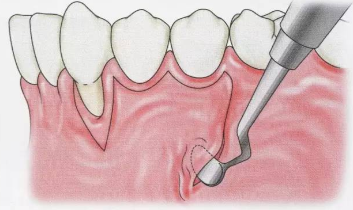

牙周刮治的器械和手法!